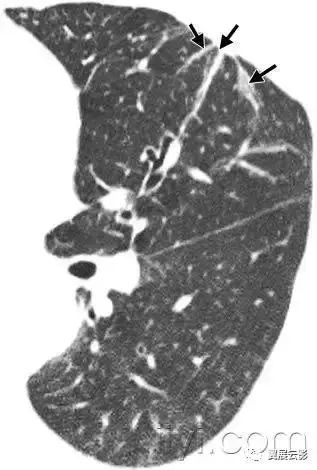

七十一、牵拉性支气管扩张或者细支气管扩张

CT:牵拉性支气管扩张和细支气管扩张是由于周围肺纤维化牵拉导致的支气管和细支气管的不规则扩张。扩张的气道可以如图所示,可以是囊状(支气管)或者是小囊状(细支气管)。多发囊样气道变形与单纯性纤维化所致蜂窝征难以鉴别。